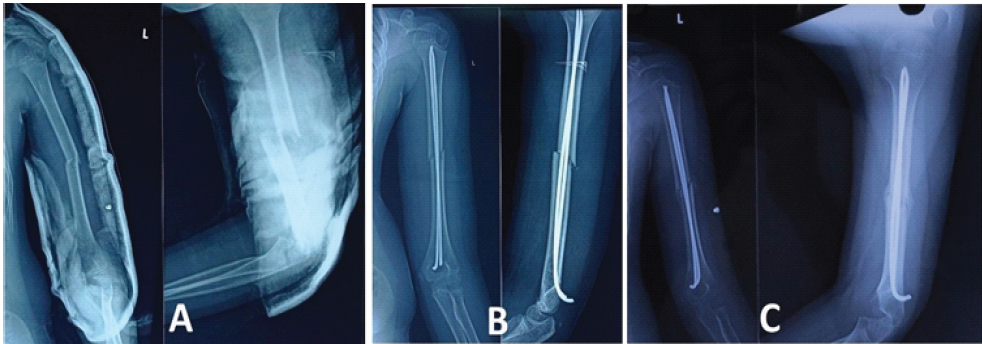

A 14-year-old boy suffered a closed fracture of the middle third of the left humerus (Fig. 5a) following a road traffic accident, involving a fall from a moving auto rickshaw. Despite initial conservative management with cast application, the fracture was found to be displaced, necessitating surgical intervention (Fig. 5b). Fracture union occurred within 16 weeks, with no reported complications. Implant removal was done at 4 months. The patient was followed up for 60 months, indicating a favorable outcome with no residual issues and full ROM in the elbow.

Figure 5: (a) Pre-operative X-ray of Patient 3, (b) Immediate post-operative X-ray of Patient 3.